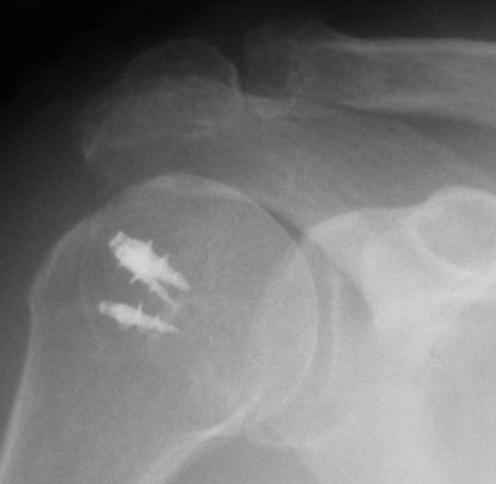

Физический активный мужчина 50 лет в мае 2009 года был оперирован на правом плечевом суставе. Выполнялся открытый шов надостной мышцы и субакромиальная декомпрессия по поводу ее частичного разрыва и импиджмент синдрома III степени. Послеоперационный период протекал без осложнений. Гипсовая иммобилизация в положении отведения плеча до 45 градусов в течение 6 недель.В последующем, несмотря на активные занатия ЛФК, сформировалась приводяще-внутриротационная контрактура оперированного сустава (отведение до 80 градусов, наружная ротация до 15 градусов. Болевого синдрома нет, при пассивном отведении плеча создается впечатление "механического" препятствия движению.На контрольных рентгенограммах складывается впечатление о сформировавшемсся верхнем подвивихе головки правой плечевой кости, как о причине контрактуры. Хотелось бы услышать мнение коллег о такттике дальнейшего лечения.

Верхний подвывих в такой ситуации может быть проявлением ротаторной артропатии, как следствия более массивного, чем частичный разрыв сухожилия надостной мыщцы, повреждения вращательной манжеты. И значит нужно думать о том, насколько полно восстановлена манжета, адекватно ли был расценен объем ее повреждения. Что за шов применялся? Якорных винтов не видно. И почему гипсовая иммобилизация? Есть прекрасные надувные отводящие подушки, позволяющие ранние движения.

В качестве примера - снимки до и после восстановления целостности вращательной манжеты после 3-хмесячной давности полного разрыва. Видно, что верхний подвывих устранен.